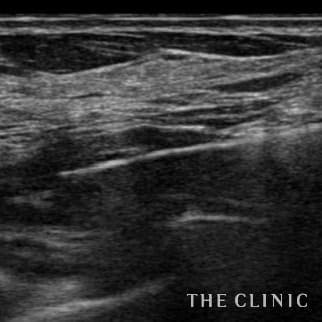

半年前に他院でアクアフィリング豊胸を行いましたが、バストの変形やしこりに悩み除去手術を希望しました。 見た目には右胸内側上部と左胸内側下部に不自然な盛り上がりとしこりを認めました。エコーではアクアフィリングのしこりが散在し、一部は塊になっていました。 アクアフィリングは生理食塩水で溶解されますが、完全には溶解せず固まっていますので、吸引して除去しました。治療の概要 アクアフィリング除去+コンデンスリッチ豊胸:乳腺用エコーを用いて、バスト内の状態を確認。その後、生理食塩水でアクアフィリングを溶解する。溶解仕切れない場合には、注射器で吸い出し除去。アクアフィリング の除去後、バストの皮下にコンデンスリッチファット(老化細胞や不純物を取り除いて濃縮させた自己脂肪)を注入。 施術費用 アクアフィリング 除去(会員料金):¥600,000(税込¥660,000)/溶解1部位